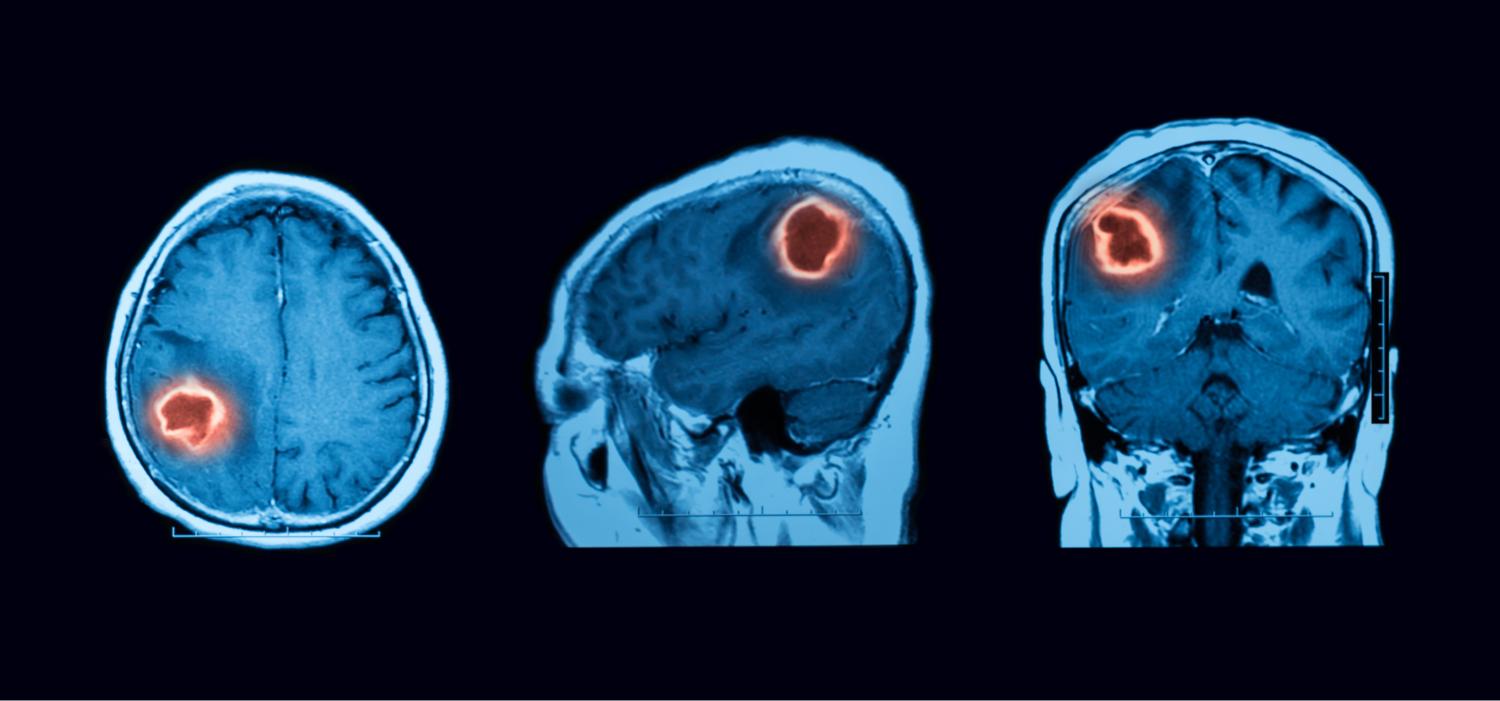

A Next-Generation Oncolytic Immunotherapy Engineered for Precision, Power, and Safety

DNX-2401 is an oncolytic immunotherapy designed to fulfill the dual requirements of high potency and safety. To accomplish this, two stable genetic changes in the adenovirus genome were engineered that cause it to replicate selectively in retinoblastoma (Rb) pathway-deficient cells and infect tumor cells efficiently. Results from preclinical and clinical studies indicate that DNX-2401 (1) replicates in human tumors, (2) elicits tumor necrosis, (3) triggers intratumoral immune cell infiltration, and (4) can lead to long-term tumor destruction.

$10.8 Million CPRIT Grant Award

The Cancer Prevention & Research Institute of Texas (CPRIT) provided $10.8 million grant to advance the development and commercialization of an innovative oncolytic adenovirus therapy for glioblastoma (GB), one of the most aggressive brain cancers.